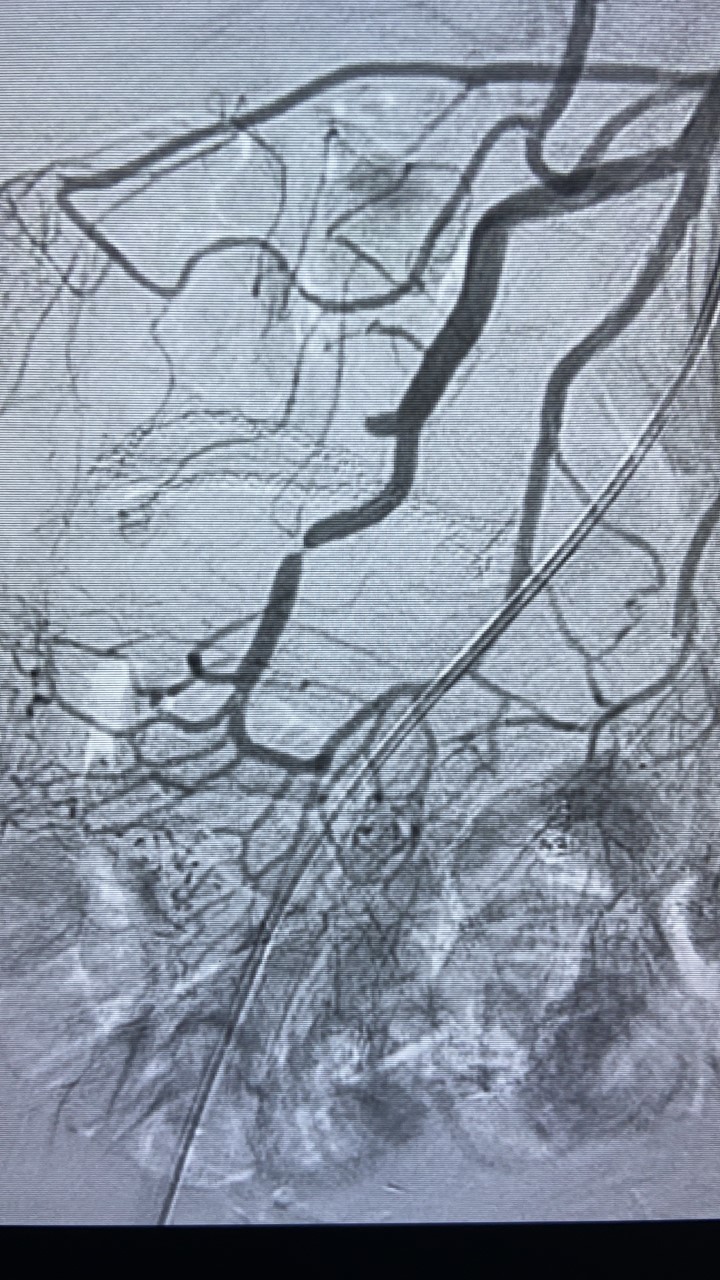

Vascular

Diagnóstico:

Angiografía de malformaciones vasculares.